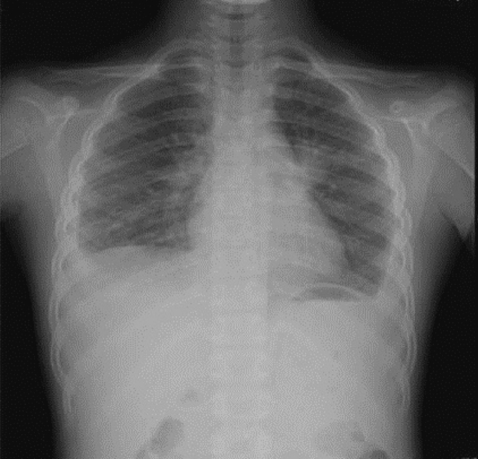

On admission, her vital signs were as follows: body temperature, 37.8℃; heart rate, 90/min; respiratory rate, 24/min; and blood pressure, 100/70 mmHg. On examination, she looked very ill and her breathing sounds were decreased on both sides of the lower chest. Moderate tenderness was detected in the right flank and the right inguinal area. A chest radiograph indicated pleural effusion (Fig. 1), and abdominal sonography revealed an inflammatory lesion in the right psoas muscle (Fig. 2). Her total white blood cell (WBC) count was 26,900 cells/mm3, hemoglobin level was 10.7 g/dl, erythrocyte sedimentation rate (ESR) was 75 mm/hr, and C-reactive protein concentration was 71 mg/dl. The patient also presented with hypereosinophilia (66%), and the total serum IgE value higher than 2,500 IU/ml. Because her dietary history and laboratory findings were indicative of a parasitic infection, we performed a serum antibody test using ELISA and examined her stool, sputum, and pleural fluid specimens [11]. No evidence of parasite eggs in the stool or sputum specimen was obtained, but ELISA was positive for P. westermani in the serum, with an optical density (OD) of 0.619 (cut-off OD: 0.255). The pleural fluid obtained by thoracentesis revealed the following findings: WBC, 26,200 cells/mm3 (neutrophils, 25%; lymphocytes, 72%); pH, 7.129; proteins, 8.2 g/dl; albumin, 2.1 g/dl; glucose, 5 mg/dl; and turbid appearance. Gram staining, culture studies, and tuberculosis- PCR (TB-PCR) in the pleural fluid, however, were negative.

One month after the first admission, the eosinophil count in the peripheral blood and the total serum IgE value were still high (eosinophils, 37.4%; IgE, 1,094 IU/ml). The follow-up chest radiograph showed improvements of the left pleural effusion, but persistence of the right pleural effusion (Fig. 3A). She was, therefore, readmitted to the hospital, and the pleural fluid was drained using a pigtail catheter.